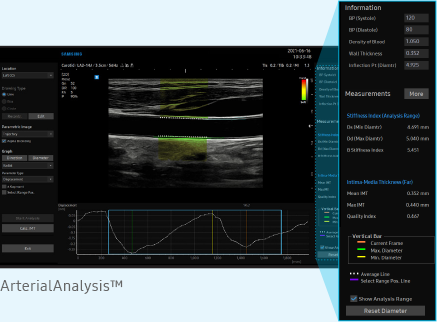

Sistemul ArterialAnalysis detectează modificările funcționale ale vaselor, furnizând valori de măsurare precum rigiditatea, grosimea intimă-media și pulsul de viteză comun. artera carotida. Deoarece schimbările funcționale apar înaintea modificărilor morfologice, această tehnologie sprijină diagnosticarea precoce a bolilor cardiovasculare.